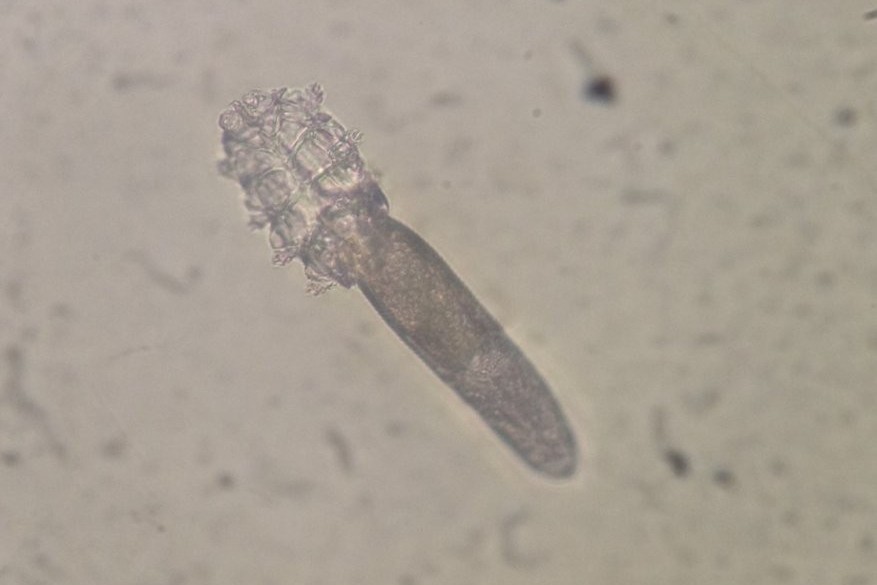

Typical eye problems associated with Stevens-Johnson syndrome include conjunctivitis, ulceration of the eyelids, inflammation inside the eye (iritis), corneal blisters and corneal perforation. After the acute stage of the disease, conjunctival and corneal scarring (Fig 2), which can lead to a decrease or loss of vision, are common.